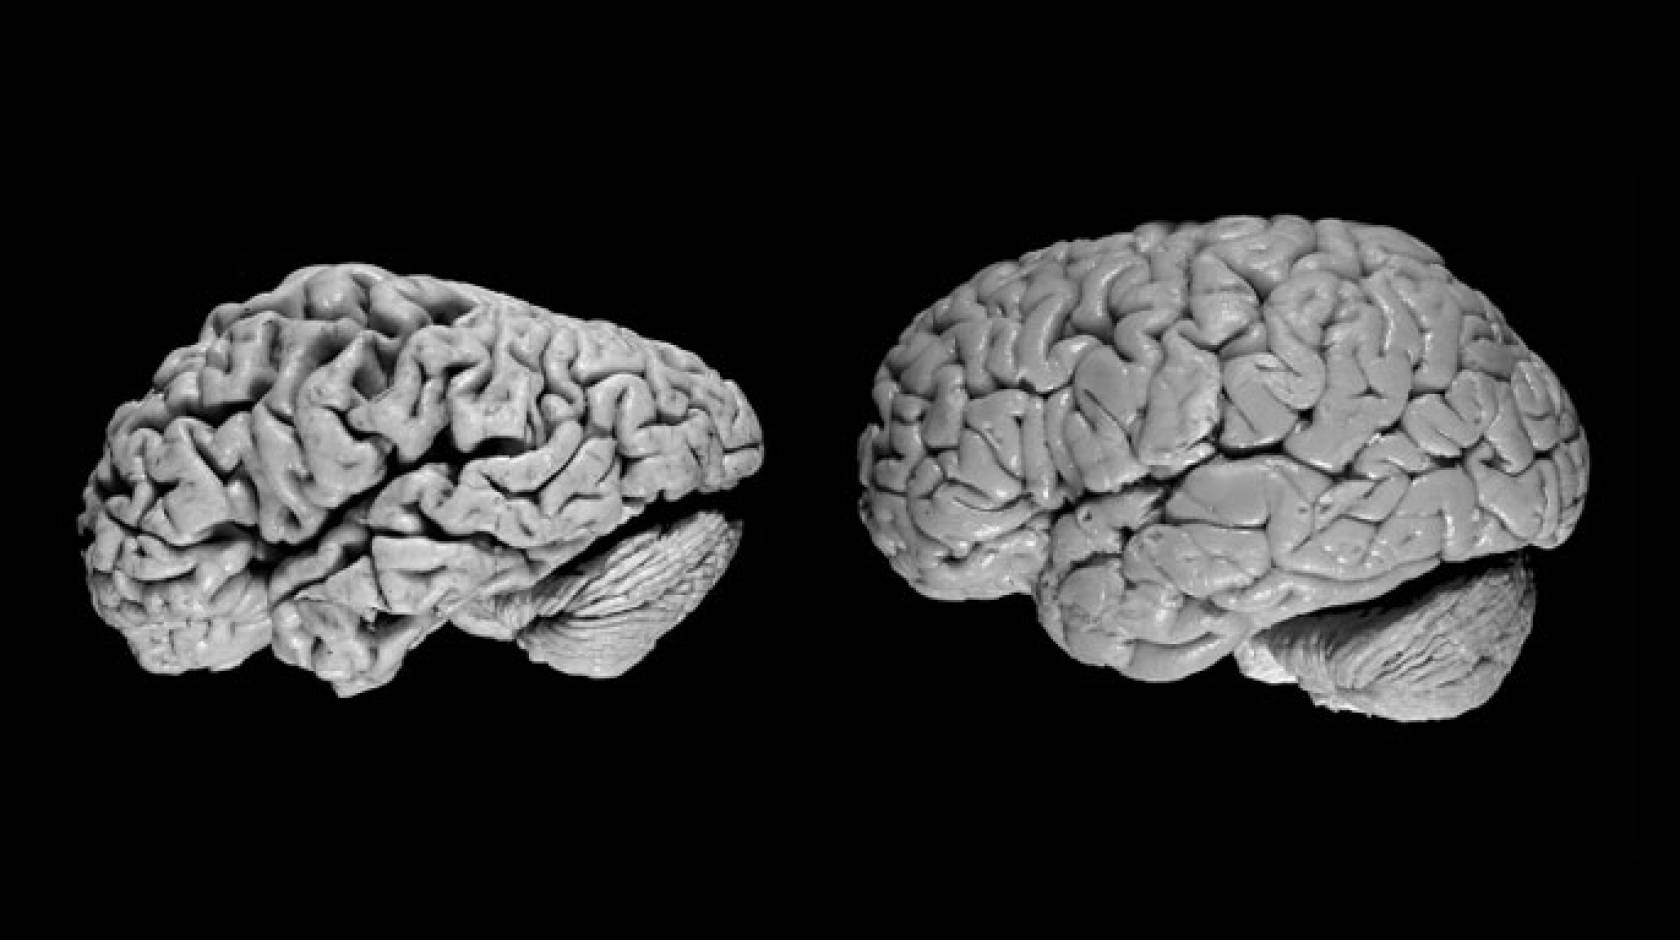

Studies of each brain specimen involve a complex and lengthy process of dissection, tissue staining, processing, analysis, synthesis, diagnoses and cataloging, said neuropathologist Brittany Dugger, assistant professor in the Department of Pathology and Laboratory Medicine and corresponding author on the paper.

Dugger and her colleagues looked at different regions of the brain such as the frontal cortex, hippocampus and cerebellum for amyloid plaques, which are markers of Alzheimer’s disease, and appear as sunbursts outside of the cell. They also looked for neurofibrillary tangles inside the cell that appear under the microscope as tiny balls of “tangled” hair, and that can also indicate Alzheimer’s disease. To tease out cerebrovascular disease, they used special stains that reveal infarctions to the trained eye, the pathologic manifestations of a stroke.